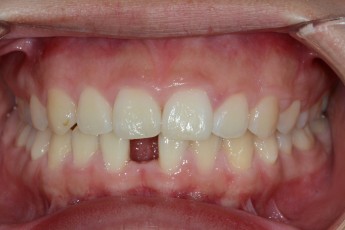

BEFORE & AFTER

- 매복치교정